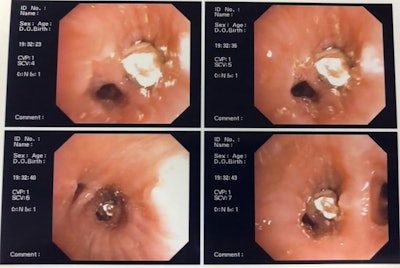

Clinicians then assessed the patient's bronchus using an orotracheal intubation cannula along with a flexible bronchoscope and basket clamp. They chose this method because it has a lower risk of morbidity and mortality, the authors noted.

The scope passed freely through the patient's trachea without alteration of its caliber and without causing mucosal lesions. Using the scope, the team visualized the dental crown, which was obliterating the man's lower lobe bronchus in his right lung.

Clinicians used the basket clamp to grab the upper premolar dental prosthetic crown and then used the cannula to remove it. The procedure was completed without complications, and the patient was reintubated. Approximately one hour passed from the time the clinicians identified the tooth until its removal.